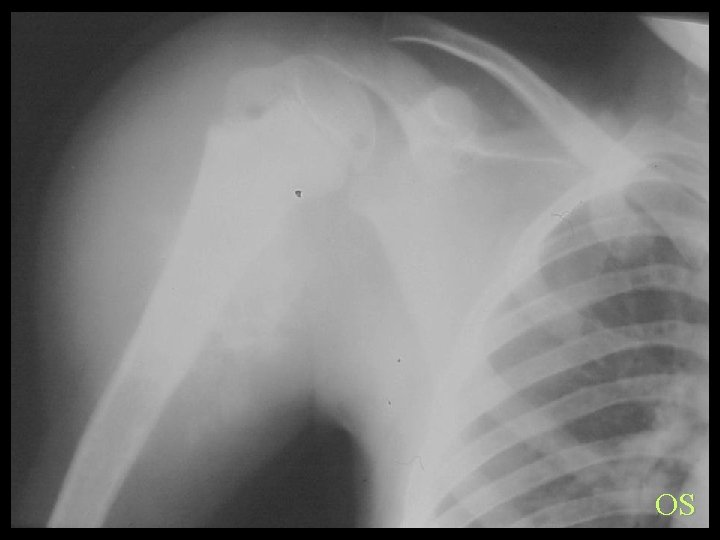

OS